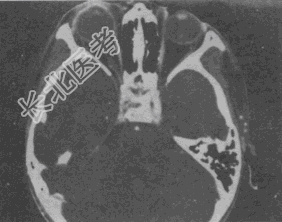

- 单项选择题女,46岁, 自述左眼视物不清约3个月,CT扫描如图所示, 正确的描述或诊断是

A、双侧眼球未见病变

B、左侧玻璃体内偏后方见絮状高密度影

C、双侧眼环形态密度正常

D、考虑视网膜脱离

E、考虑玻璃体内出血